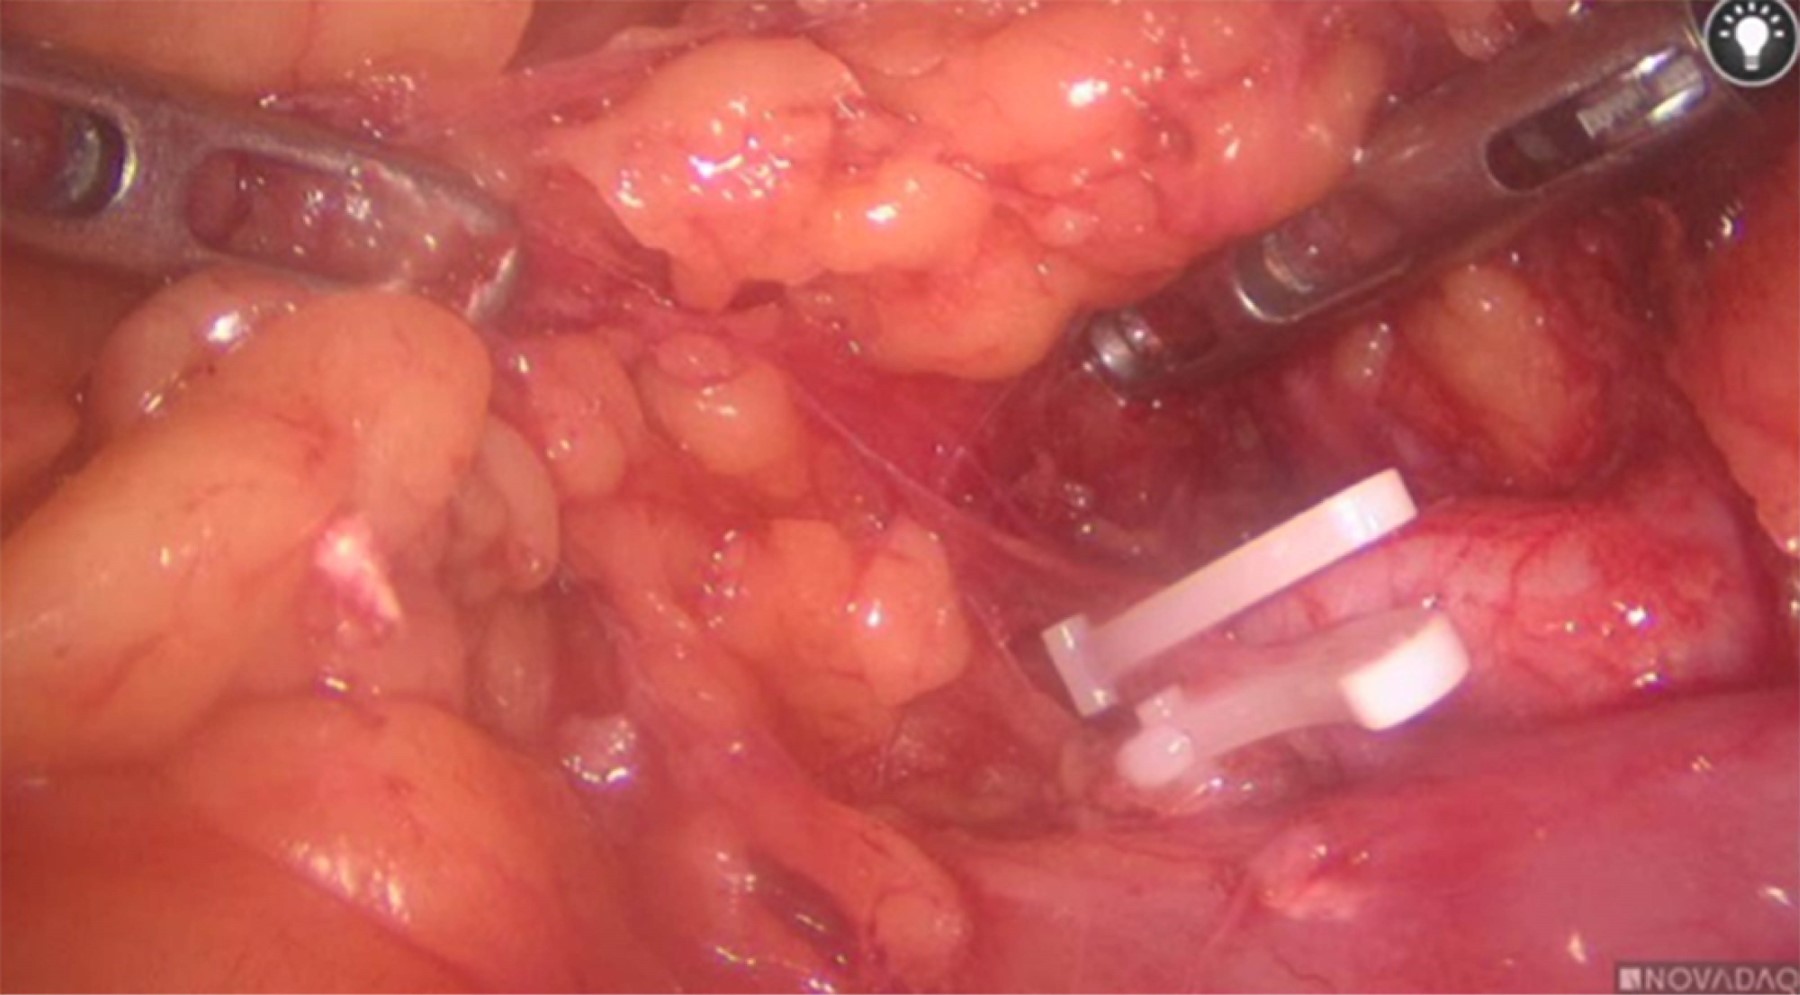

• 4. Disección hasta hilio renal visualizándose vena, posterior disección hasta visualizar vena adrenal encontrándose una principal y dos vasos de neoformación, manejados con hemolocks (Figuras 3).

Figura 3